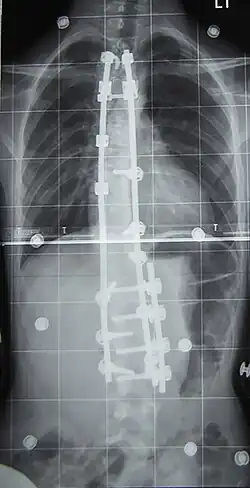

Surgery is usually recommended by orthopedists for curves with a high likelihood of progression (i.e., greater than 45–50° of magnitude), curves that would be cosmetically unacceptable as an adult, curves in people with spina bifida and cerebral palsy that interfere with sitting and care, and curves that affect physiological functions such as breathing.[106][107]

Surgery is indicated by the Society on Scoliosis Orthopaedic and Rehabilitation Treatment (SOSORT) at 45–50°[4] and by the Scoliosis Research Society (SRS) at a Cobb angle of 45°.[108] SOSORT uses the 45–50° threshold as a result of the well-documented, plus or minus 5° measurement error that can occur while measuring Cobb angles.[108]

Surgeons who specialize in spine surgery perform surgery for scoliosis. To completely straighten a scoliotic spine is usually impossible, but for the most part, significant corrections are achieved.[109]

The two main types of surgery are:[110]

- Anterior fusion: This surgical approach is through an incision at the side of the chest wall.

- Posterior fusion: This surgical approach is through an incision on the back and uses metal instrumentation to correct the curve.

One or both of these surgical procedures may be needed. The surgery may be done in one or two stages and, on average, takes four to eight hours.